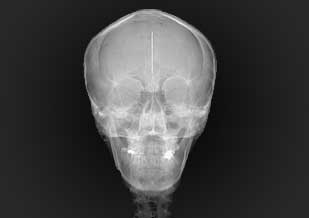

Telerradiografía frontal de cráneo

Estudio extraoral del cual se obtiene una imagen frontal de las estructuras de interés, imprescindible para el estudio de asimetrías faciales. Dentro de técnicas frontales, se incluyen aquellas que permiten observar senos paranasales, fundamentalmente maxilares.